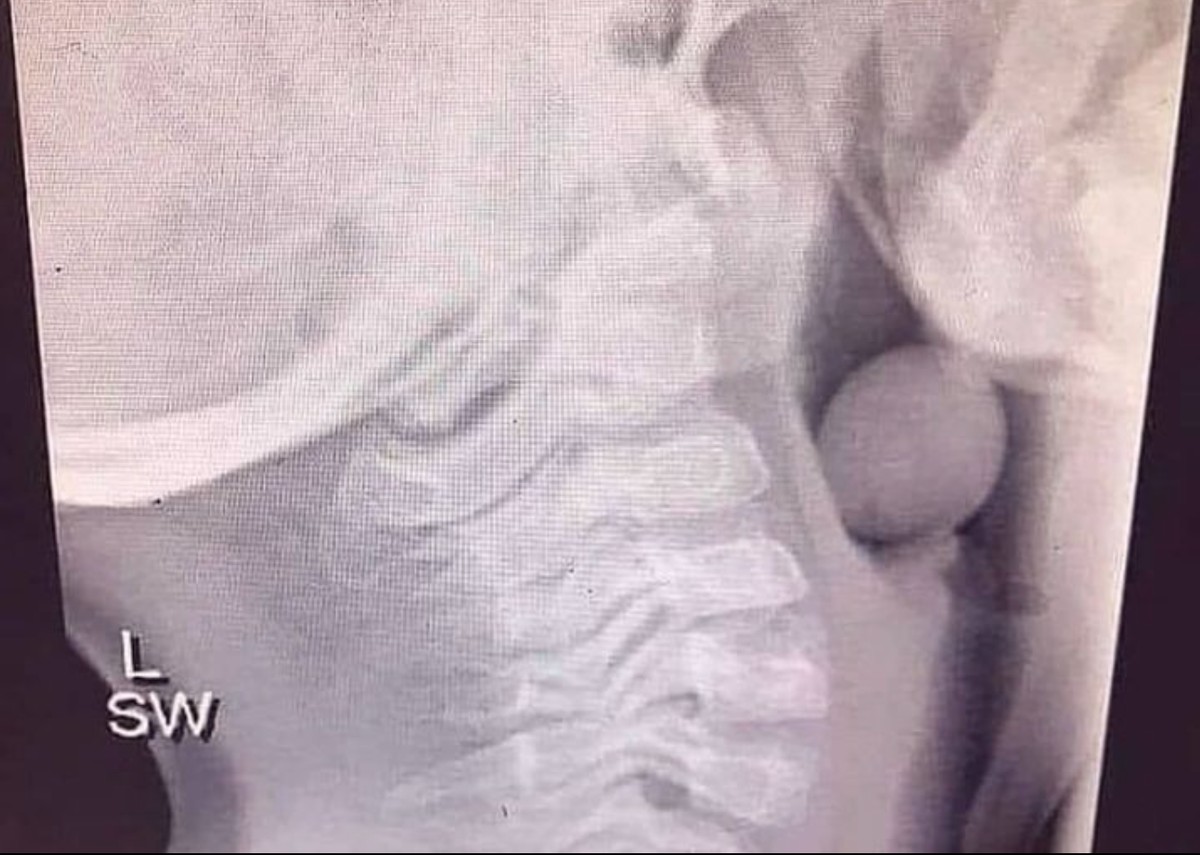

В дыхательных путях застряла еда

В дыхательных путях застряла еда 99 фото